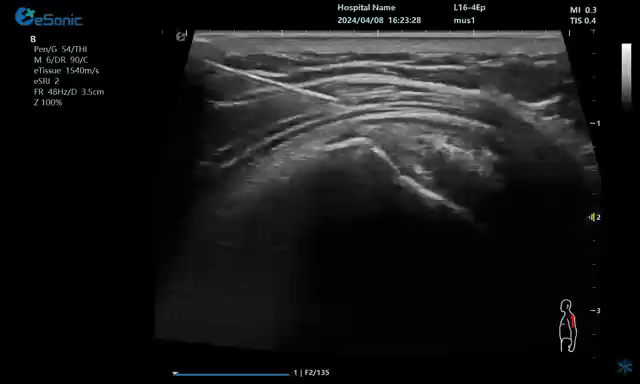

一、超声引导下注射准确性在尸体上研究

在超声引导下注射准确性尸体研究方面,以美国MavoClinic的康复医师SmithJ和FinnoffJT为代表的肌骨超声的开拓者们,做了大量的开创性研究工作,奠定了超声引导下注射准确性的科学基础。